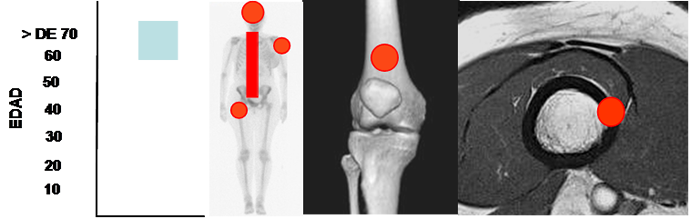

Fig 187. Mieloma.

Mayor frecuencia en mayores de 60 años. Predominio columna, cráneo y parte proximal del fémur y húmero. Lesión diafisiaria, de ubicación central.